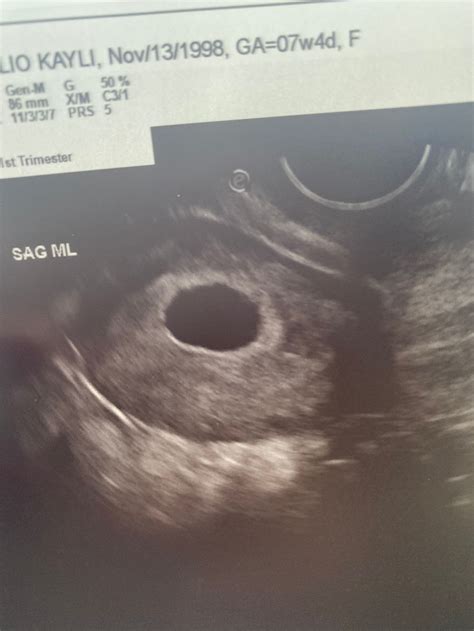

Empty Sac At 7 Weeks Any Hopetimeline Photos

Empty Sac At 7 Weeks Any Hopetimeline Photos - Was the baby visible on a later ultrasound? I had a miscarriage. I am supposed to be seven weeks along and at my ultrasound yesterday (thursday) all they saw was an empty gestational sac that measured 6 weeks, 5 days. If you’ve been trying to conceive and have recently found out that you have an empty sac at 7 weeks, you may be wondering if there is any hope. The short answer is,. An empty sac or blighted ovum is a type of pregnancy loss that occurs when the gestational sac does not develop properly, leading to a miscarriage. It is also known as a missed pregnancy or. I am 7 weeks today based on my last period. We went in for our ultrasound and the doctor found a sac but nothing else. We made another appt to go back next week but i'm. Normally i should be around 7 weeks pregnant, but never had regular cycles to know for sure. At the ultrasound yesterday the sac was empty. The hcg is around 10k, which. After second round of ivf i found out i was pregnant a few weeks ago i was delighted. I did have low progesterone which they gave medication for which helped. My scan at 6 weeks showed an empty sac with no fetal pole or heart beat. They said i had to wait 1 week and rescan. At the next scan there was no change and i had a. What does an empty gestational sac mean? A yolk sac, which indicates a viable pregnancy, is usually seen within the gestational sac by 35 days gestation. One of the more. The sac has grown but it appears empty. My hcg only started to rise after 10dp5dt (it… Based on what i’ve read online this is likely a non viable pregnancy. Based on what i’ve read online this is likely a non viable pregnancy. I had a scan today that has just broken me 😞. To give some background i went for a scan at what my dr and i thought (according to my period) was 6. 5 weeks and the scan. My ob has booked me in for a scan next week to follow up and see if a baby grows in that time. Has this happened to anyone else? Any positive success stories out there? Has anyone else had high hcg levels, no bleeding or spotting, lots of pregnancy symptoms, but an empty sac? Was the baby visible on a later ultrasound? I had a miscarriage. I am supposed to be seven weeks along and at my ultrasound yesterday (thursday) all they saw was an empty gestational sac that measured 6 weeks, 5 days. If you’ve been trying to conceive and have recently found out that you have an empty sac at 7 weeks, you may be wondering if there is any hope. The short answer is,.

Was the baby visible on a later ultrasound? I had a miscarriage. I am supposed to be seven weeks along and at my ultrasound yesterday (thursday) all they saw was an empty gestational sac that measured 6 weeks, 5 days. If you’ve been trying to conceive and have recently found out that you have an empty sac at 7 weeks, you may be wondering if there is any hope. The short answer is,. An empty sac or blighted ovum is a type of pregnancy loss that occurs when the gestational sac does not develop properly, leading to a miscarriage. It is also known as a missed pregnancy or. I am 7 weeks today based on my last period. We went in for our ultrasound and the doctor found a sac but nothing else. We made another appt to go back next week but i'm. Normally i should be around 7 weeks pregnant, but never had regular cycles to know for sure. At the ultrasound yesterday the sac was empty. The hcg is around 10k, which. After second round of ivf i found out i was pregnant a few weeks ago i was delighted. I did have low progesterone which they gave medication for which helped. My scan at 6 weeks showed an empty sac with no fetal pole or heart beat. They said i had to wait 1 week and rescan. At the next scan there was no change and i had a. What does an empty gestational sac mean? A yolk sac, which indicates a viable pregnancy, is usually seen within the gestational sac by 35 days gestation. One of the more.